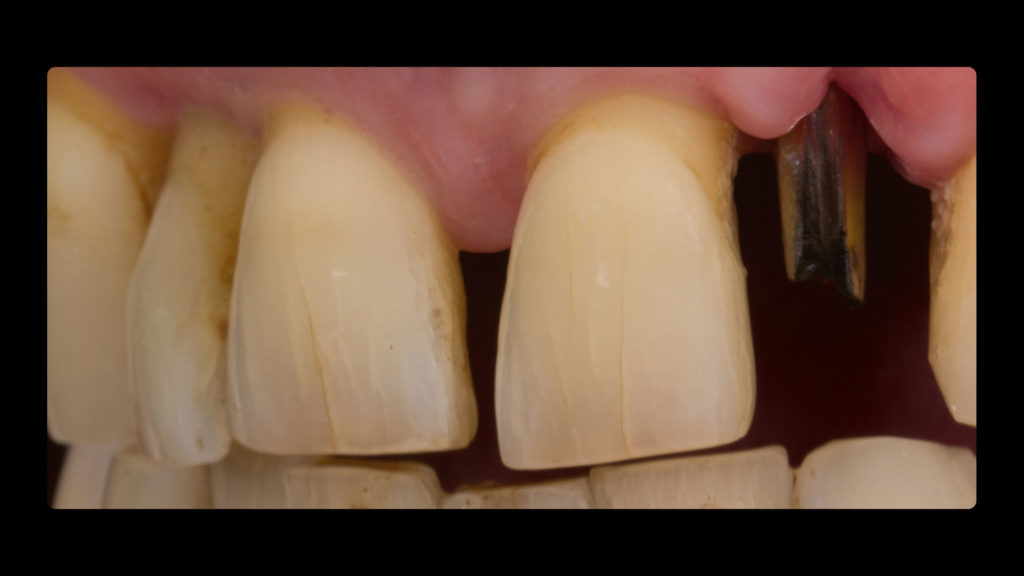

Die Implantatkrone sollte metallkeramisch gelöst werden, was wiederum bedeutete, dass für die entsprechend designte Implantatkrone ein CAD/CAM-gestützt gefertigtes Abutment (vorgefertigt, Schweden & Martina) mit einer Metallkeramik (Ceramco 3, Dentsply Sirona) verblendet werden musste. Es wurde eine zementierte Lösung gewählt, weshalb es keinen Schraubenkanal gab und somit keine Probleme mit dessen Austritt gelöst werden mussten. In den Abbildungen 6a und 6b sind die DSLR-Aufnahmen des Behandlers dargestellt. Die Referenzfarbmuster vermitteln die ungefähre Zahnfarbe, aber nicht alle Informationen und Merkmale, die für die Rekonstruktion des natürlichen Zahns vonnöten sind. Indem man die Belichtung reduziert und den Kontrast sowie die Brillanz in einem Bildbearbeitungsprogramm wie Lightroom (Adobe) erhöht, lässt sich die Histoanatomie des natürlichen Zahns besser darstellen (Abb. 6c).

Auf Wunsch des Patienten sollte der zu rekonstruierende laterale Schneidezahn die Charakteristika des mittleren Inzisiven 21, also seines direkten Nachbarzahns aufweisen. Normalerweise hätte man sich an dem noch verbliebenen lateralen Schneidezahn im ersten Quadranten orientiert, doch leider war auch dessen Zustand nicht ideal, sodass auch dieser in Bälde rekonstruiert werden sollte (Abb. 7a und b). Bei der eingehenden Betrachtung des Zahns 21 stellten wir zwar eine gewisse Ähnlichkeit mit den vom Zahnarzt gewählten Farbmusterzähnen fest, erkannten aber auch relevante Unterschiede. Aus diesem Grund starteten wir die laborseitige Analyse mit polarisierten Aufnahmen (Abb. 8a und b). Da der Patient 49 Jahre alt war, suchten wir gezielt nach charakteristischen Merkmalen natürlicher älterer Zähne und und wurden auch fündig.